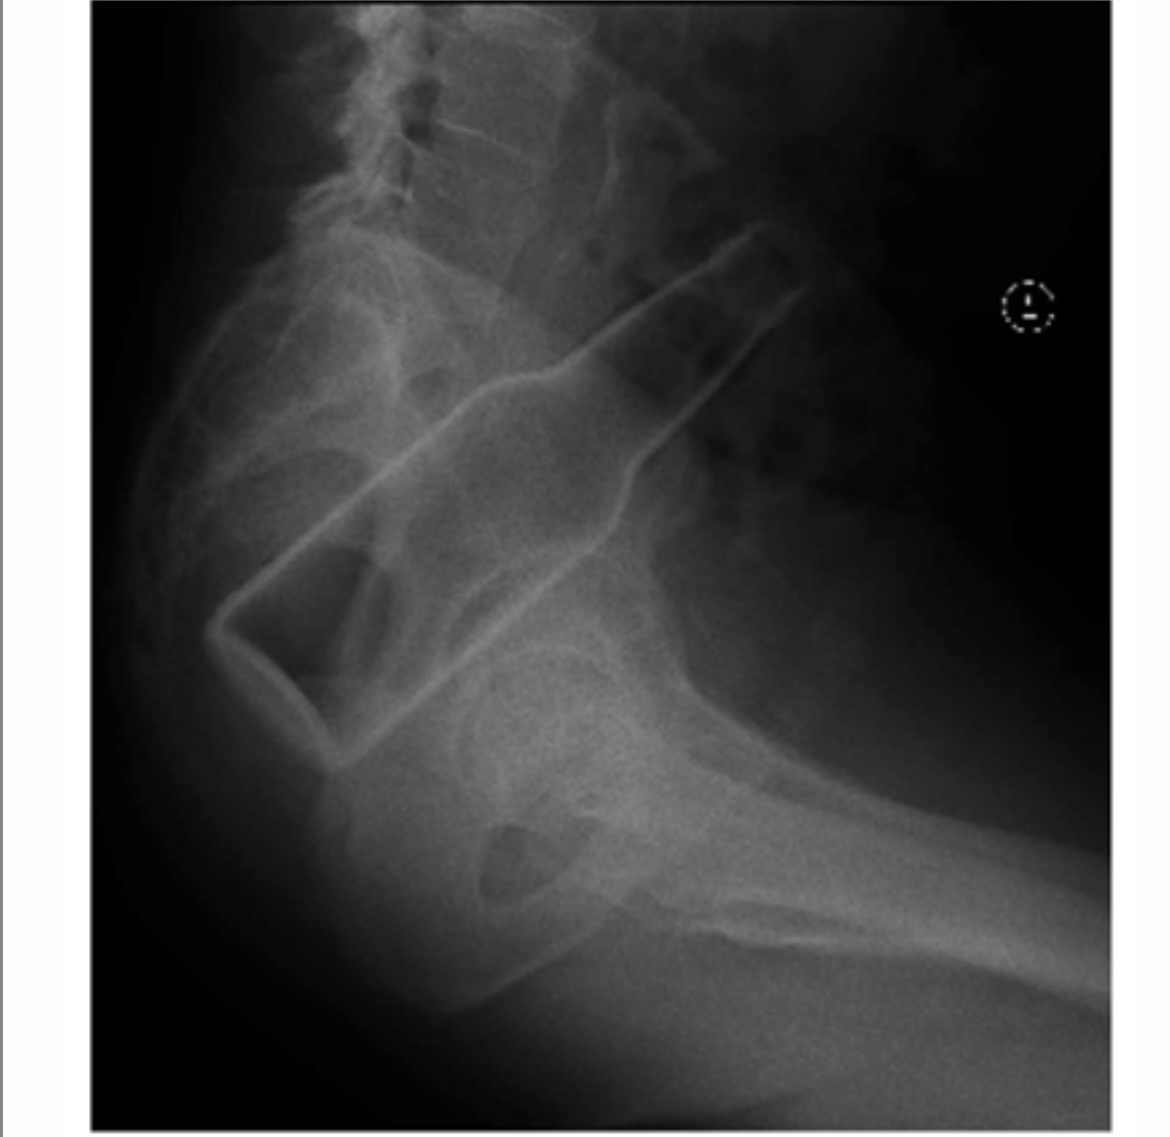

• Diagnostic Imaging: X-rays, CT scans, or ultrasound help identify the object’s size, location, and any associated damage.

• Surgical Intervention: Required when the object is sharp, embedded, or causing complications like perforation.